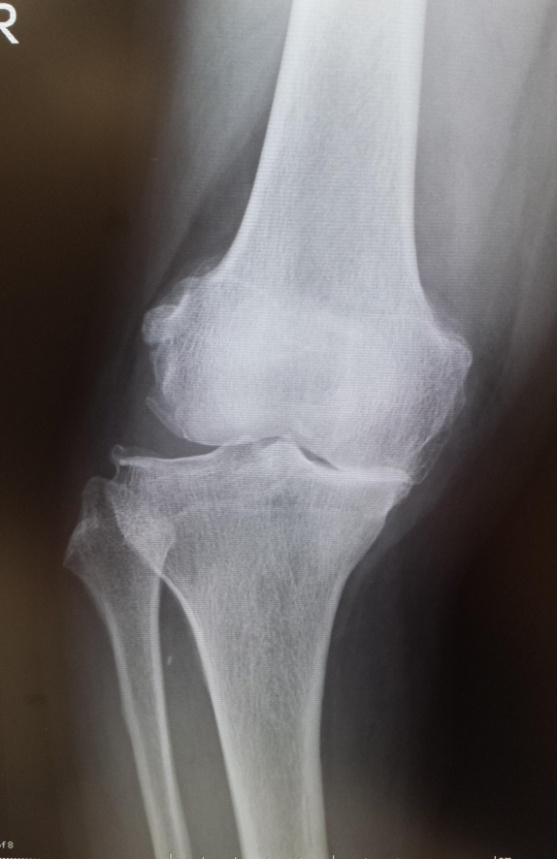

当院でおこなった人工膝関節全置換術(TKA)

手術前